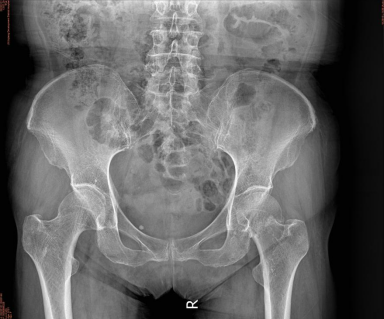

經醫師檢查,給予拍片后診斷為左側股骨頸骨折,需住院治療,在患者完善所有檢查后,骨科醫生經過與家屬溝通,詳細講解患者病情及治療方案后,決定為老人行人工髖關節置換術,經過充分術前準備后,在骨科、麻醉科、手術室等多科共同協助下,由骨科胡斌主任親自主刀,為劉婆婆實施人工髖關節置換術,因術前制定了完整的圍術期管理方案,成功縮短了手術時間,減少了術中出血,手術過程十分順利,術后三天劉婆婆能起床活動站立行走,一周后順利康復出院。